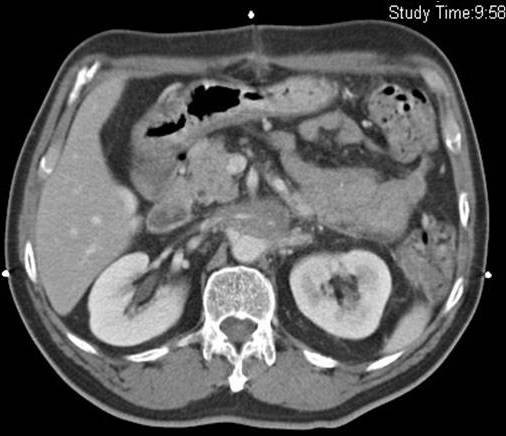

Figure 1From: Post radiation chylous ascites: a case reportPreoperative abdominal CT scan showing retroperitoneal mass encasing the right renal vein (arrow).Back to article page